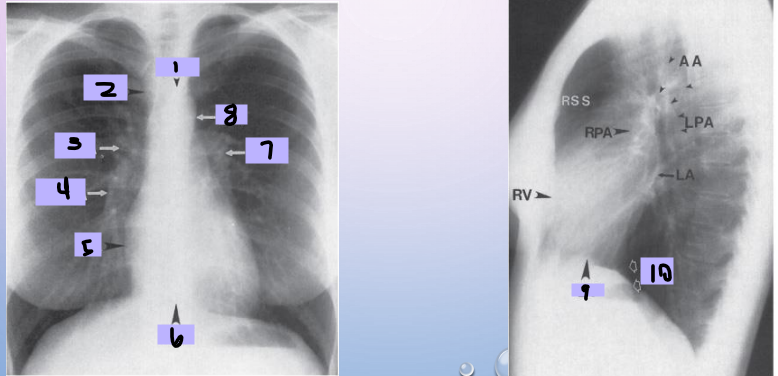

Aortic arch

#1

Superior vena cava

#2

Right pulmonary artery

#3

Right descending pulmonary artery

#4

Right atrium

#5

Right ventricle

#6

Left pulmonary artery

#7

Descending aorta

#8

Left ventricle

#9

Inferior vena cava

#10